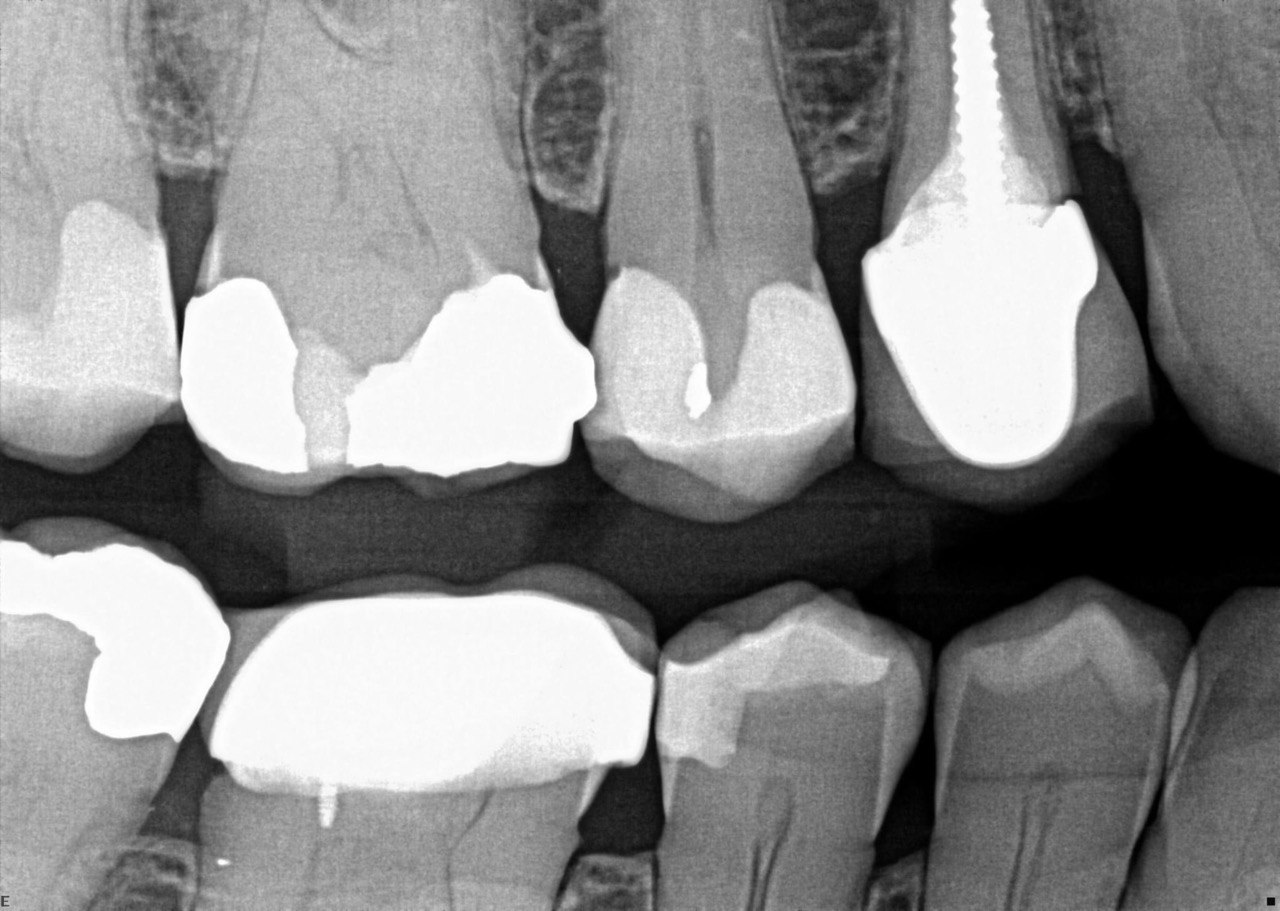

Question 1: What is the condition of the mesial surface of the tooth # 2.6?

Question 2. What is the condition of the mesial of the tooth # 2.7?

Question 3. What is the condition of the distal surface of the tooth # 2.7 and mesial surface of the tooth # 2.8 respectively?

Question 5: Which surface shows recurrent caries?

Question 6: Which surface shows recurrent caries?

Question 7: What are the options associated with the distal surface of the tooth # 2.1 and mesial surface of the tooth # 2.2 respectively?